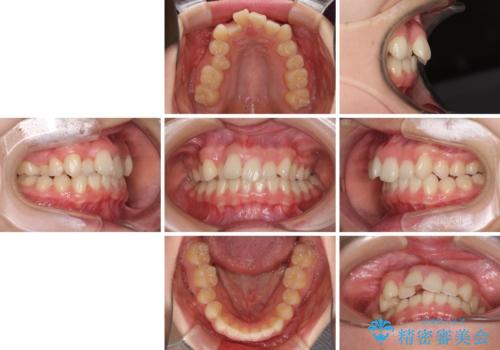

- 上顎前歯のデコボコを気にして来院された患者様です。

口元の突出感はなく、上顎のみに顕著な叢生が認められました。

上顎の左右第一小臼歯2本を抜歯し、ワイヤー装置にて歯列を整えることとしました。